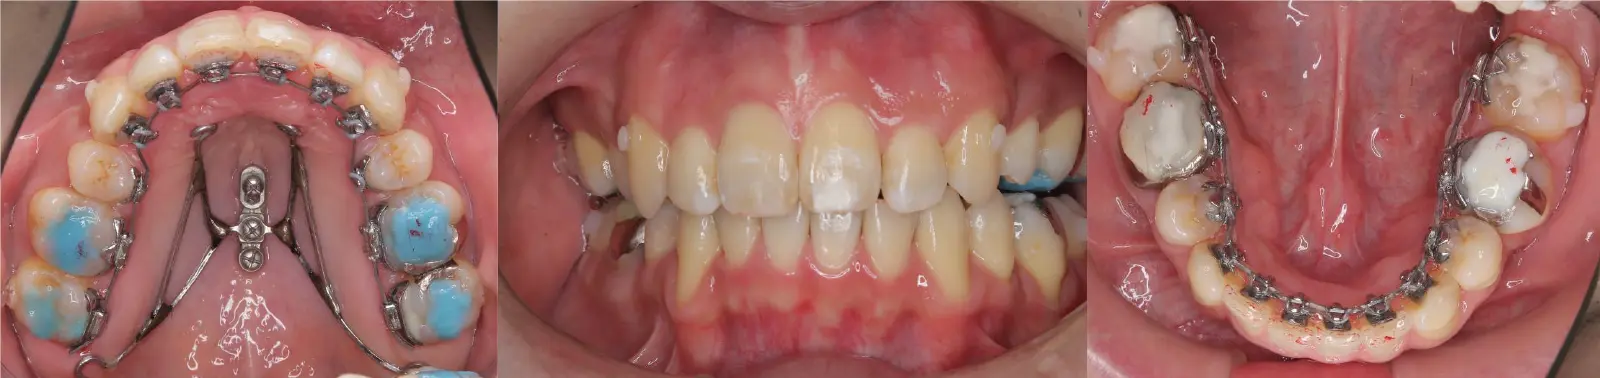

アングルⅡ級 開咬を伴う上顎前突症

- 主訴

前歯がかみ合わない

- 年齢

10代

- 治療期間

2年1ヶ月

- 治療回数

24回

- 治療に用いた主な装置

カスタムメイド型マルチブラケットタイプのデジタル矯正装置(インシグニア)

i-station(口蓋型アンカースクリュー)

- 治療費

650,000円(税別)、調整料5,000円(税別)

※伊那分院にて治療

- 抜歯部位

上顎第一小臼歯2本

下顎第二小臼歯2本